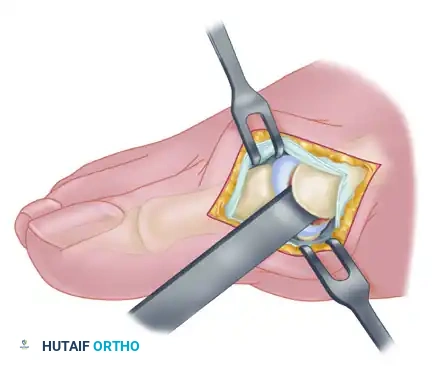

The L-Shaped Capsulotomy Alternative

Depending on surgeon preference and the specific anatomical presentation, an inverted-L shaped capsulotomy may be utilized instead of a longitudinal incision.

- Make the capsular incision in an inverted-L shape. Raise the dorsal flap deep to the nerve and veins until the accessory slip of the extensor hallucis longus (EHL) tendon is visualized in the proximal portion of the incision.

- Begin the incision proximally on the dorsomedial side of the first metatarsal shaft, approximately 2 to 3 mm medial to the accessory slip of the EHL tendon. Carry the incision down to the bone at the level of the first metatarsal joint, extending it proximally for 4 to 6 cm.

- Make the transverse limb of the capsular incision at the level of the joint, stopping 2 to 3 mm from the tibial sesamoid bone. This transverse limb effectively transects the capsular insertion of the abductor hallucis muscle.

- Beginning on the plantar aspect of the incision, carefully remove the capsule from the medial eminence from the inside out. Direct the small-bladed knife down the slope of the eminence to avoid "buttonholing" the capsule at the junction of the medial eminence and the metatarsal shaft.

- Free the capsule subperiosteally on its dorsomedial surface, and retract it proximally and plantarward.

- Insert one small Hohmann retractor over the dorsolateral surface of the metatarsal head and another beneath the head at the head-neck junction. Distract and plantarflex the hallux to fully expose the articular surface of the metatarsal head. Evaluate the cartilage for degenerative changes and assess the orientation of the distal metatarsal articular angle (DMAA).

- Reduce the hallux congruently onto the metatarsal head. If the hallux remains in more than 15 degrees of valgus after reduction, a concomitant distal metatarsal osteotomy (e.g., Chevron) is definitively required.